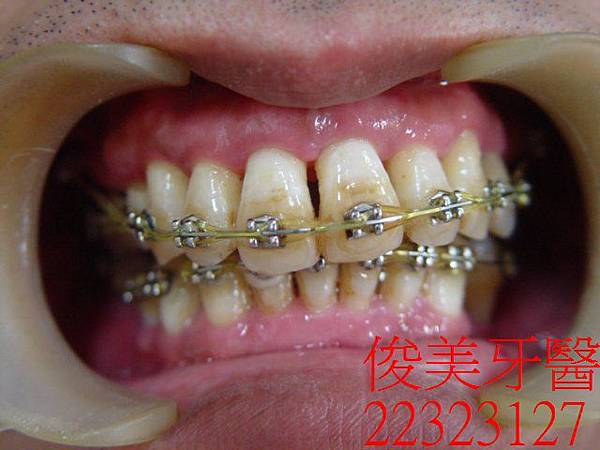

在牙結石清除後,施行牙周病治療,採雷射牙周病治療,過程舒適,術後無痛、不流血。

術後牙周狀況有明顯改善。

治療中~~~有大幅改善咬合。

上、下顎落差持續縮小。

患者因骨頭較硬,進展速度稍慢,但仍有顯著進步。